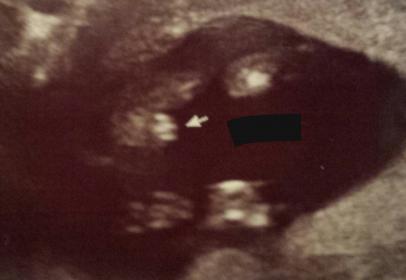

Tech was pretty certain on gender. Want to see how your guesses match up.

potty shot! Do you see the same?

Thanks. Let me add that this is a 14+3 shot

I'll go with girl, at 14+3 I would think the little doodle would stick out a bit more?

Maybe girl?